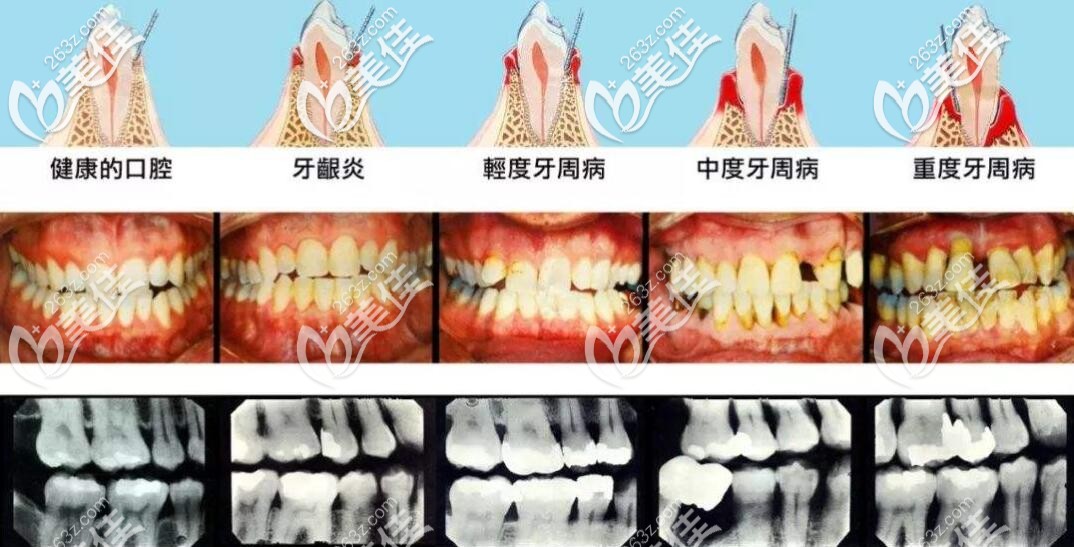

牙齿刷牙、啃苹果流血,牙齿变形、松动、咀嚼无、牙龈红肿,口臭,警惕牙周炎,是导致成年人牙齿脱落的主要原因。

牙周发炎不是上火,不是吃点药就好,治本的关键更不在祛火,而是控制牙菌斑。牙菌斑由大量细菌、食物残屑等组成。控制牙菌斑,养成良好的生活习惯和口腔卫生意识起到决定性的作用。